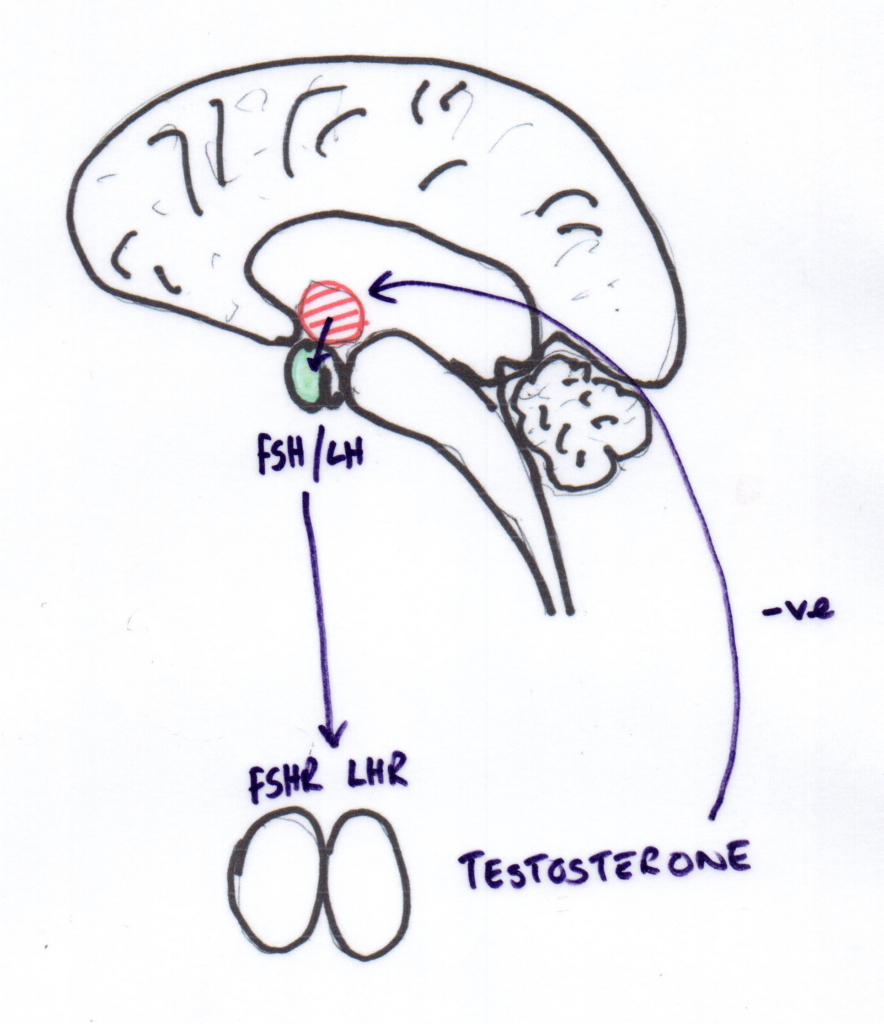

Biological Focus: HPG Axis and LHR

Existing literature suggests possible links between:

- Post-desexing endocrine shifts

- Gonadotrophin signalling

- Connective tissue integrity

For this reason, hypothalamic–pituitary–gonadal (HPG) axis signalling—specifically luteinising hormone receptor (LHR) expression—was selected as a biologically plausible focus for correlation.axis involvement, and specifically luteinising hormone receptor (LHR) expression, was selected as a biologically plausible focus for correlation. Images below show the hormones in an entire patient and a desexed patient.